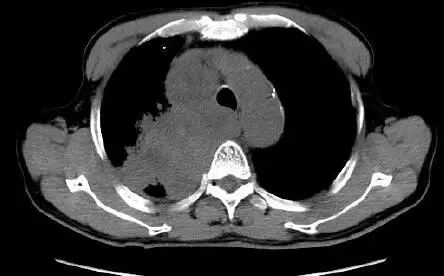

癌,乃魔鬼,张牙舞爪的魔鬼,甚至是吸血鬼。所以,肺癌的CT的特征就是不规则的肿块,有毛刺、分叶,牵拉胸膜引起胸膜凹陷,烂糟糟的空洞,吸血鬼征:血管向肿块聚拢,以供肿瘤吸血。

这么多征象一起存在,肺癌妥妥的,接近100%。

典型肺癌。

看吧,肺癌就是不规矩。

看吧,肺癌就是乱七八糟。

肺癌:吸血鬼特征。